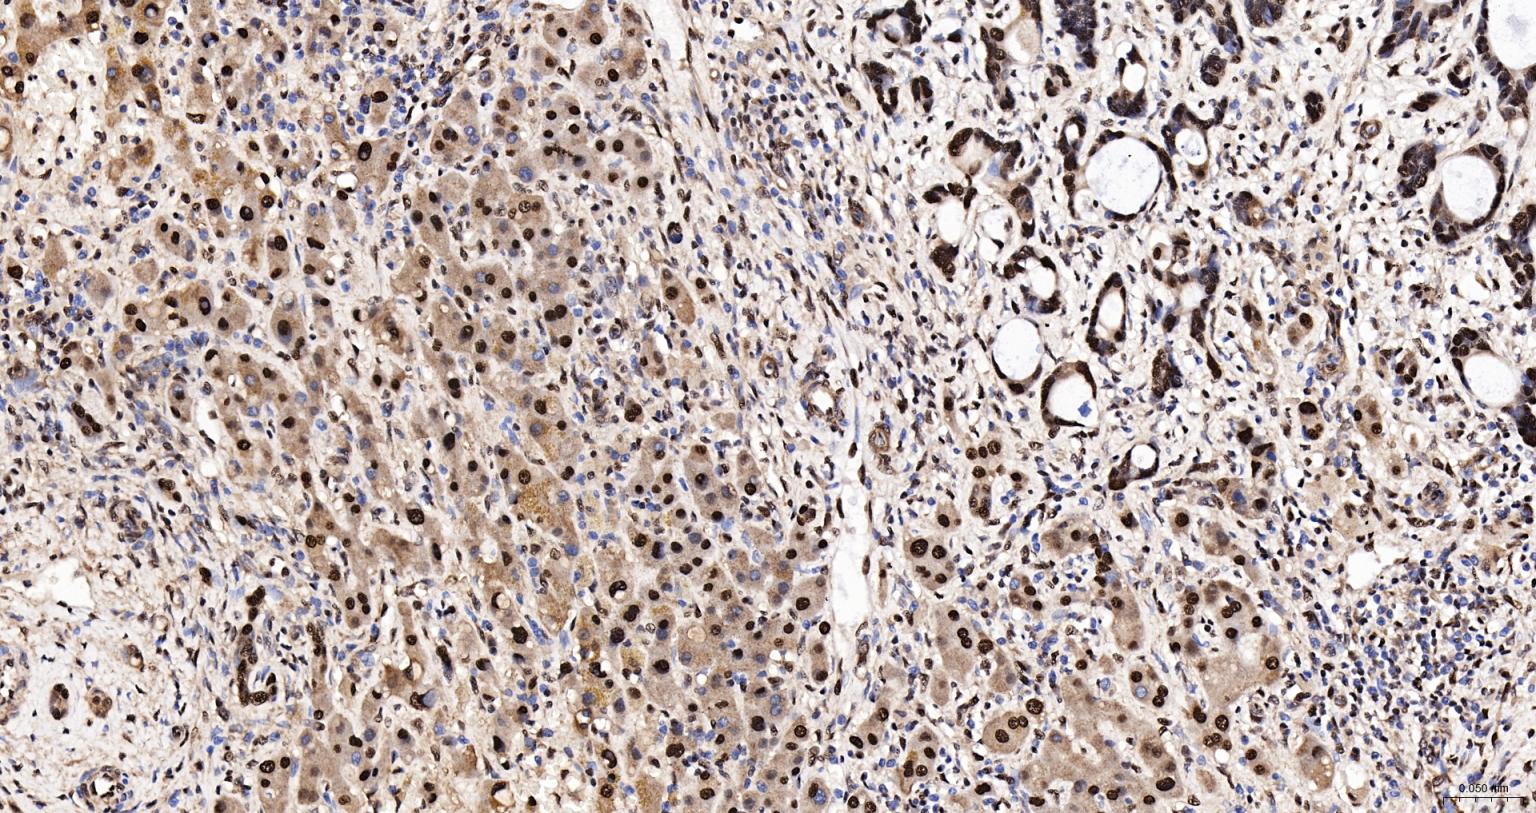

Paraformaldehyde-fixed, paraffin embedded Human Liver Cancer; Antigen retrieval by boiling in sodium citrate buffer (pH6.0) for 15 min; The section was incubated with HDGF Monoclonal Antibody, Unconjugated (bsm-62928R) at 1:200 overnight at 4°C, followed by conjugation to the bs-0295G-HRP and DAB (C-0010) staining.

Paraformaldehyde-fixed, paraffin embedded Human Liver Cancer; Antigen retrieval by boiling in sodium citrate buffer (pH6.0) for 15 min; The section was incubated with HDGF Monoclonal Antibody, Unconjugated (bsm-62928R) at 1:200 overnight at 4°C. Followed by conjugated Goat Anti-Rabbit IgG antibody (Red, bs-0295G-BF594), DAPI (blue, C02-04002) was used to stain the cell nuclei.